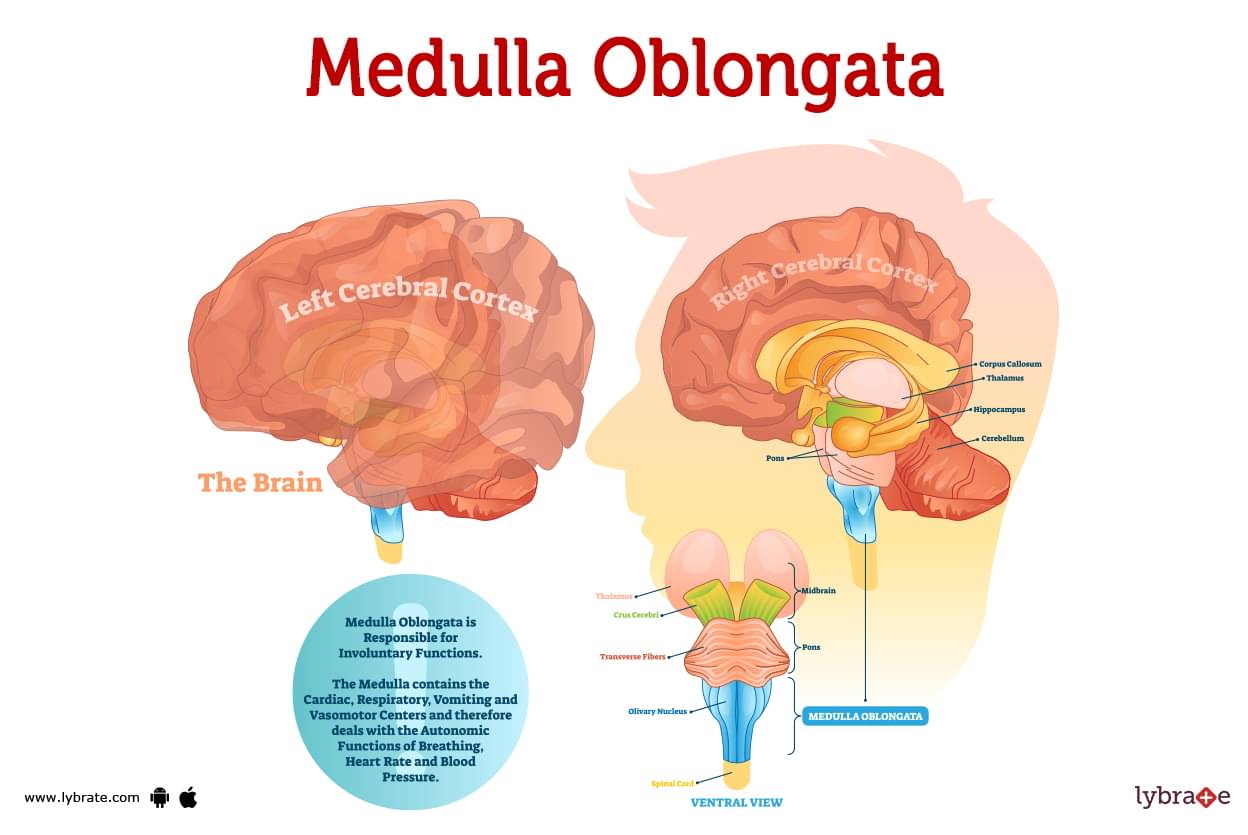

Medulla Oblongata: What It Is, Function & Anatomy

Know Your Brain: Medulla Oblongata

Medulla oblongata | Description, Anatomy, & Function | Britannica

Medulla oblongata | Encyclopedia | Anatomy.app | Learn anatomy

Medulla oblongata | Description, Anatomy, & Function | Britannica

Snapshot: What is the Medulla Oblongata? - National Ataxia Foundation

Medulla Oblongata: Location, Function, Injury, and Illness

The Anatomy of the Medulla Oblongata

The Medulla Oblongata - Internal Structure - Vasculature

Medulla Oblongata Location, Function, and Features

Medulla oblongata – Lancaster Glossary of Child Development

Medulla Oblongata | Facts, Position In Brain, Summary & Function

Medulla Oblongata

Medulla Oblongata: Definition, Structure And Functions

medull/o - Master Medical Terms